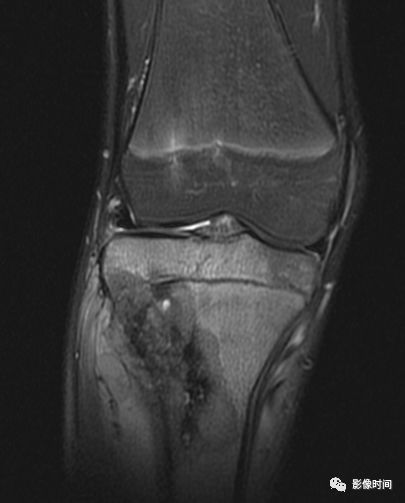

肿瘤周边的骨髓水肿表现为 T1WT 低信号和 T2WI、STIR 高信号边界模糊的片状影,软组织肿块邻近的正常软组织成分,尤其是肌肉内亦可出现水肿,表现为肿块周围沿肌束方向分布的边界模糊的片状或羽毛状影,有时可连成片。瘤周水肿常见于恶性肿瘤(图 58),但也可见于某些良性肿瘤如软骨母细胞瘤(图 59)、骨样骨瘤和骨嗜酸性肉芽肿(图 60)等。

图 59 瘤周水肿:软骨母细胞瘤